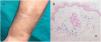

Una mujer de 66 años durante el transcurso de un ingreso hospitalario por una enfermedad de causa tromboembólica, recibió una dosis de carboximaltosa de hierro por vía intravenosa administrada en la vena cefálica del antebrazo, por tener un nivel bajo de hemoglobina. Días después, en su domicilio, observó la aparición de la mácula hiperpigmentada mostrada en la imagen (fig. 1A) en la vecindad del lugar donde se había realizado la inyección del compuesto previamente mencionado, que no se acompañaba de otra sintomatología acompañante. Tras varias semanas, la paciente acudió a las consultas externas de Dermatología para valoración.

Se realizó una biopsia cutánea en sacabocados cuyo estudio histológico mostró la existencia de una elastosis en la dermis papilar y una inflamación crónica discreta con la presencia intersticial de macrófagos pigmentados, tipo hemosiderófagos, en todo el espesor dérmico resaltados mediante la tinción de Perls (fig. 1B).

Con la correlación clínico-patológica, se estableció el diagnóstico de siderosis cutánea, secundaria a la extravasación del compuesto de hierro intravenoso.